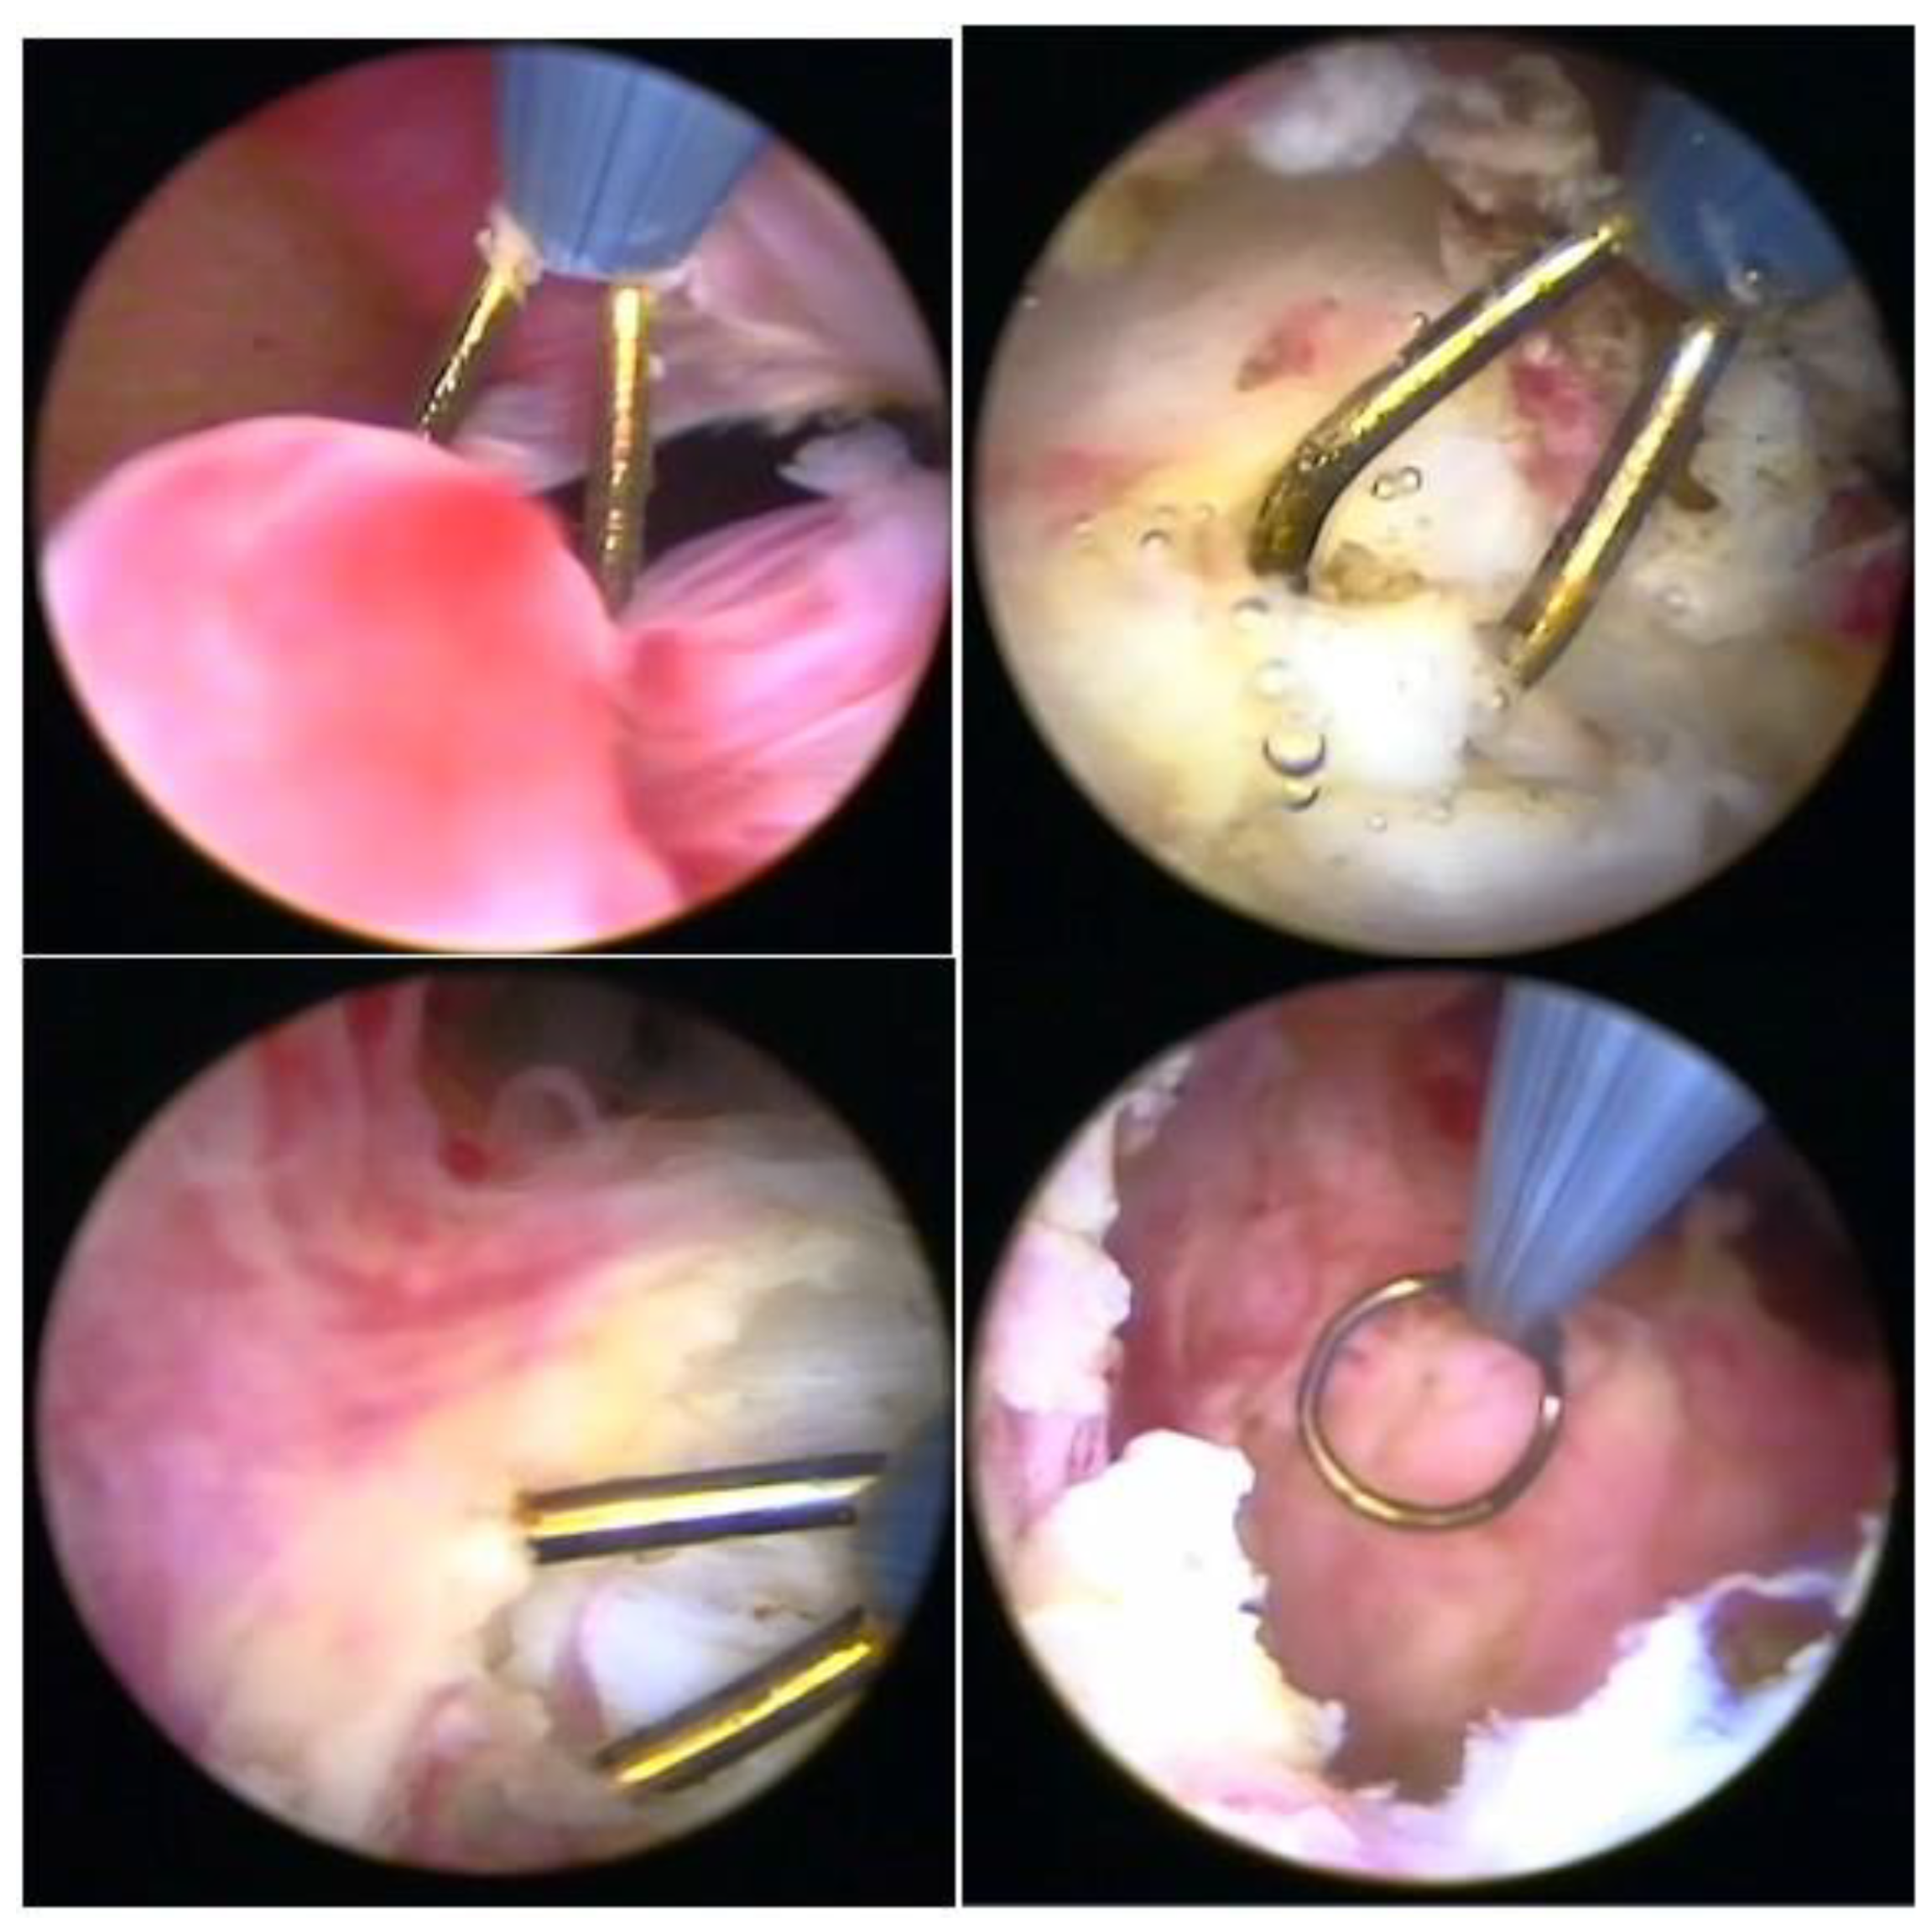

Hysteroscopy, as a method of direct visualization of the uterine cavity, offers all possible information about the intracavitary portion of the submucous myoma and a good assessment of the portion of the myoma, which is found in the myometrium, intramural portion. Thus, with hysteroscopy, it is possible to classify the submucous myoma and assess the need for other imaging methods. Another important function of hysteroscopy is to rule out other intrauterine causes of bleeding and to carry out an anatomopathological study of the endometrium or of the identified lesions, so it should, whenever possible, be indicated in the investigation (Figure 1).

3.1. Hysteroscopic Myomectomy Techniques

Myomectomy, whether laparotomic or laparoscopic, is a well-established procedure, widely performed with the goal of uterine preservation. In both approaches, the myomectomy technique is the same: incision of the serosa up to the pseudocapsule, identification of the myoma, traction and movement of the nodule, assistance in dissecting the plane of the pseudocapsule within the myometrium, and enucleation of the myoma from the uterine wall. This fibroid enucleation technique is known and performed by all gynecologists. When the pseudocapsule is reached, the chance of preserving the uterus will be greater, with less bleeding and less myometrial damage, which differs from adenomyosis resection, which does not have a pseudocapsule [21] (Figure 6).

The presentation of the techniques will make the presentation of this text more didactic, as we basically have two techniques, which can be associated or isolated, each one having its own indication of excellence. These are the enucleation technique and the slicing or myolysis technique, all of which can be performed in outpatient and inpatient hysteroscopy. The enucleation technique was described by Mazzon in 1995 [24] and Lasmar in 2001 [25]. Both techniques have the same basis for enucleation of the nodule, but Mazzon fragments the nodule until it reaches its intramural portion and then uses a “cold loop” to mobilize the fibroid, while Lasmar enucleates the entire fibroid and then slices it. The technique is to incise the endometrium around the submucosal myoma to reach the pseudocapsule (Lasmar) or to reach this plane by slicing the myoma close to the myometrium (Mazzon). Arriving at the pseudocapsule, some fibrous beams must be sectioned. The mobilization of the myoma, from the outside to the center, from front to back, progressively frees it from the myometrium, without significant bleeding and without thermal damage, with a lower risk of intravasation, as it does not cut the myometrial vessels. The mobilization of the myoma with its enucleation can be performed by all instruments, without energy, the use of scissors or tweezers being more appropriate in the outpatient clinic and Collins loop or “cold loop” in hospital hysteroscopy. The slicing technique is based on the progressive cutting of the submucosal portion of the myoma, maintaining the fragmentation of the intramural portion, leading, in most cases, to greater removal of the endometrium and myometrium, with greater thermal damage and risk of intravasation [26]. Fragmentation of the myoma can be performed with a semi-circle loop, with mono or bipolar energy, LASER fiber or morcellator. Thus, the technique of excellence in hysteroscopic myomectomy is the enucleation of the intramural portion of the submucosal myoma, mobilizing the nodule and separating it from the wall of the uterus, while fragmentation would deal with the removal of the myoma from the uterine cavity.

In our service, the most performed technique is using the 5 Fr tweezers or scissors. Initially, the endometrium is incised around the nodule until accessing the plane of the pseudocapsule; then, with the forceps or the body of the hysteroscope, entering between the nodule and the myometrium, the release is initially performed, laterally first and then centrally, until its complete release (Figure 7).

At the end, the nodule will be loose in the cavity and can be fragmented or completely removed with grasping forceps. In cases of difficulty in removing the nodule from the cavity, the patient should be instructed to return in 7 to 10 days, during which time either the nodule will be spontaneously expelled by the patient—she should be oriented about this possibility—or it will have drastically decreased in size, allowing its removal.

When using instruments with energy, we can use the bipolar Collins loop of a miniresectosope system [26] (Figure 8) or the LASER fiber to incise the endometrium around the myoma. However, all mobilization is performed mechanically with forceps, a loop, or the resectoscope itself.

Figure 1. Submucous myoma—hysteroscopic view.

Figure 7. Office hystreroscopic myomectomy with scissor.